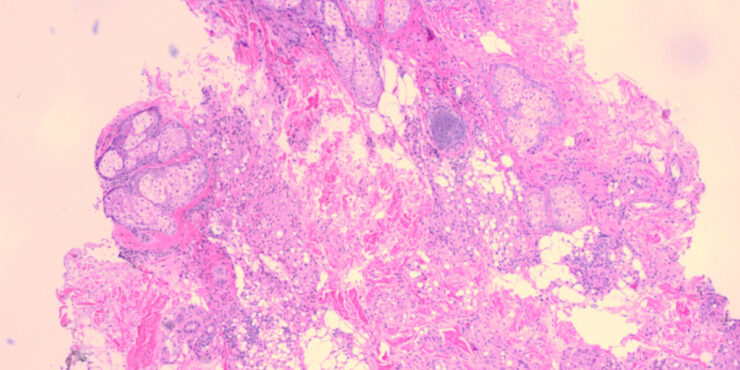

Read MoreParaffinoma = الورم البارافيني Paraffinoma Foreign-body reactions may occur following injections of oily substances such as mineral oil (paraffin) typically into the breasts , genitalia, or scalp for cosmetic purposes. These occur as irregular, plaquelike indurations of the skin and subcutaneous tissue . Ulcers or abscesses may develop. The interval between the time of injection and […]